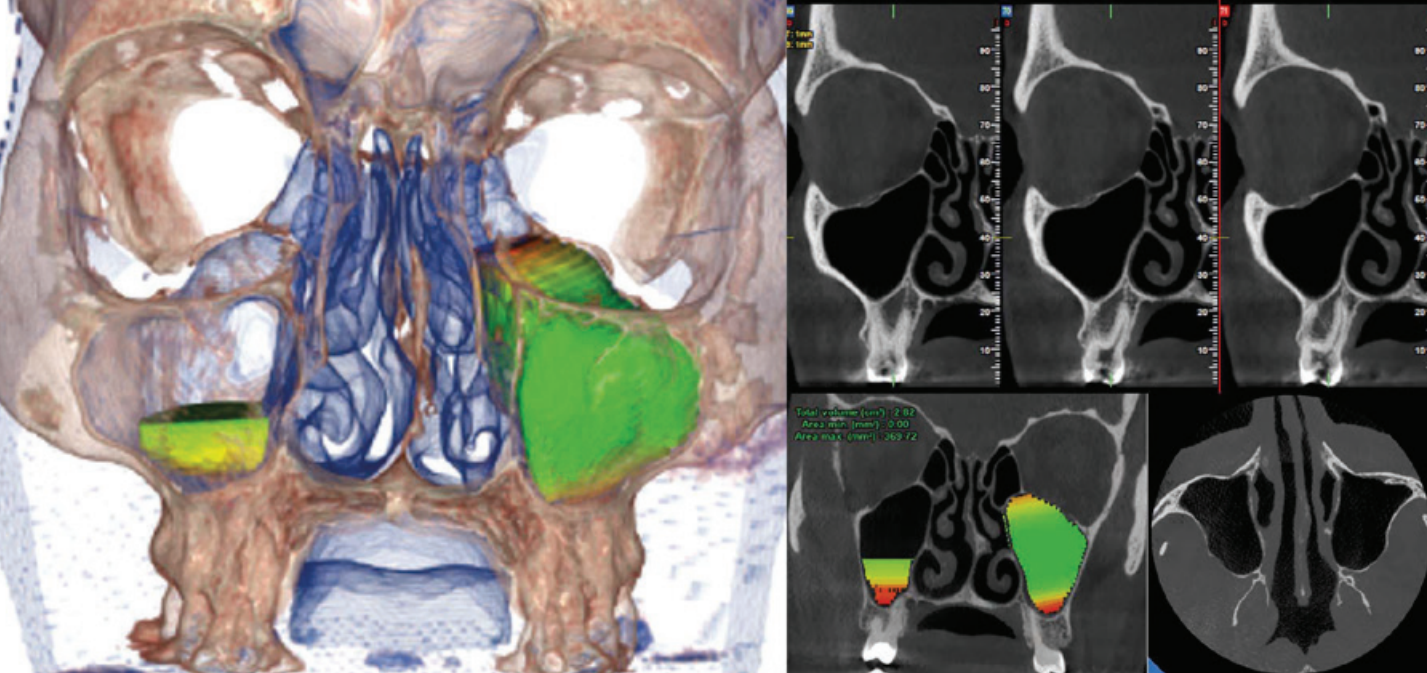

Tek bir taramada sinüsler bölgesinin görüntüsünü elde eder. Bu çekim modu, sinüs kaldırma ve hastalardaki morfolojik oranları değerlendirilmesine olanak sunmaktadır. Ayrıca hacimsel ölçüm, analiz dahil olmak üzere optimize edilmiş tedavi planlamaları olası hastalıkların dikkatle teşhis edilmesini sağlar.

İmplant bölgesini çevreleyen anatomik yapılar hakkında bilgi verir. Kemik kalitesinin değerlendirmesi ve gelişmiş IRYS yazılım özelliğiyle cerrahî prosedürlerin, ameliyat sonrası iyileşme sürelerinin en iyi şekilde planlanması mümkün olur. Bu özellik sayesinde geniş kapsamlı yazılımın implant kütüphanesinde bulunan implantların seçilip konumlandırılarak görüntüler üzerinde planlama yapılabilir.